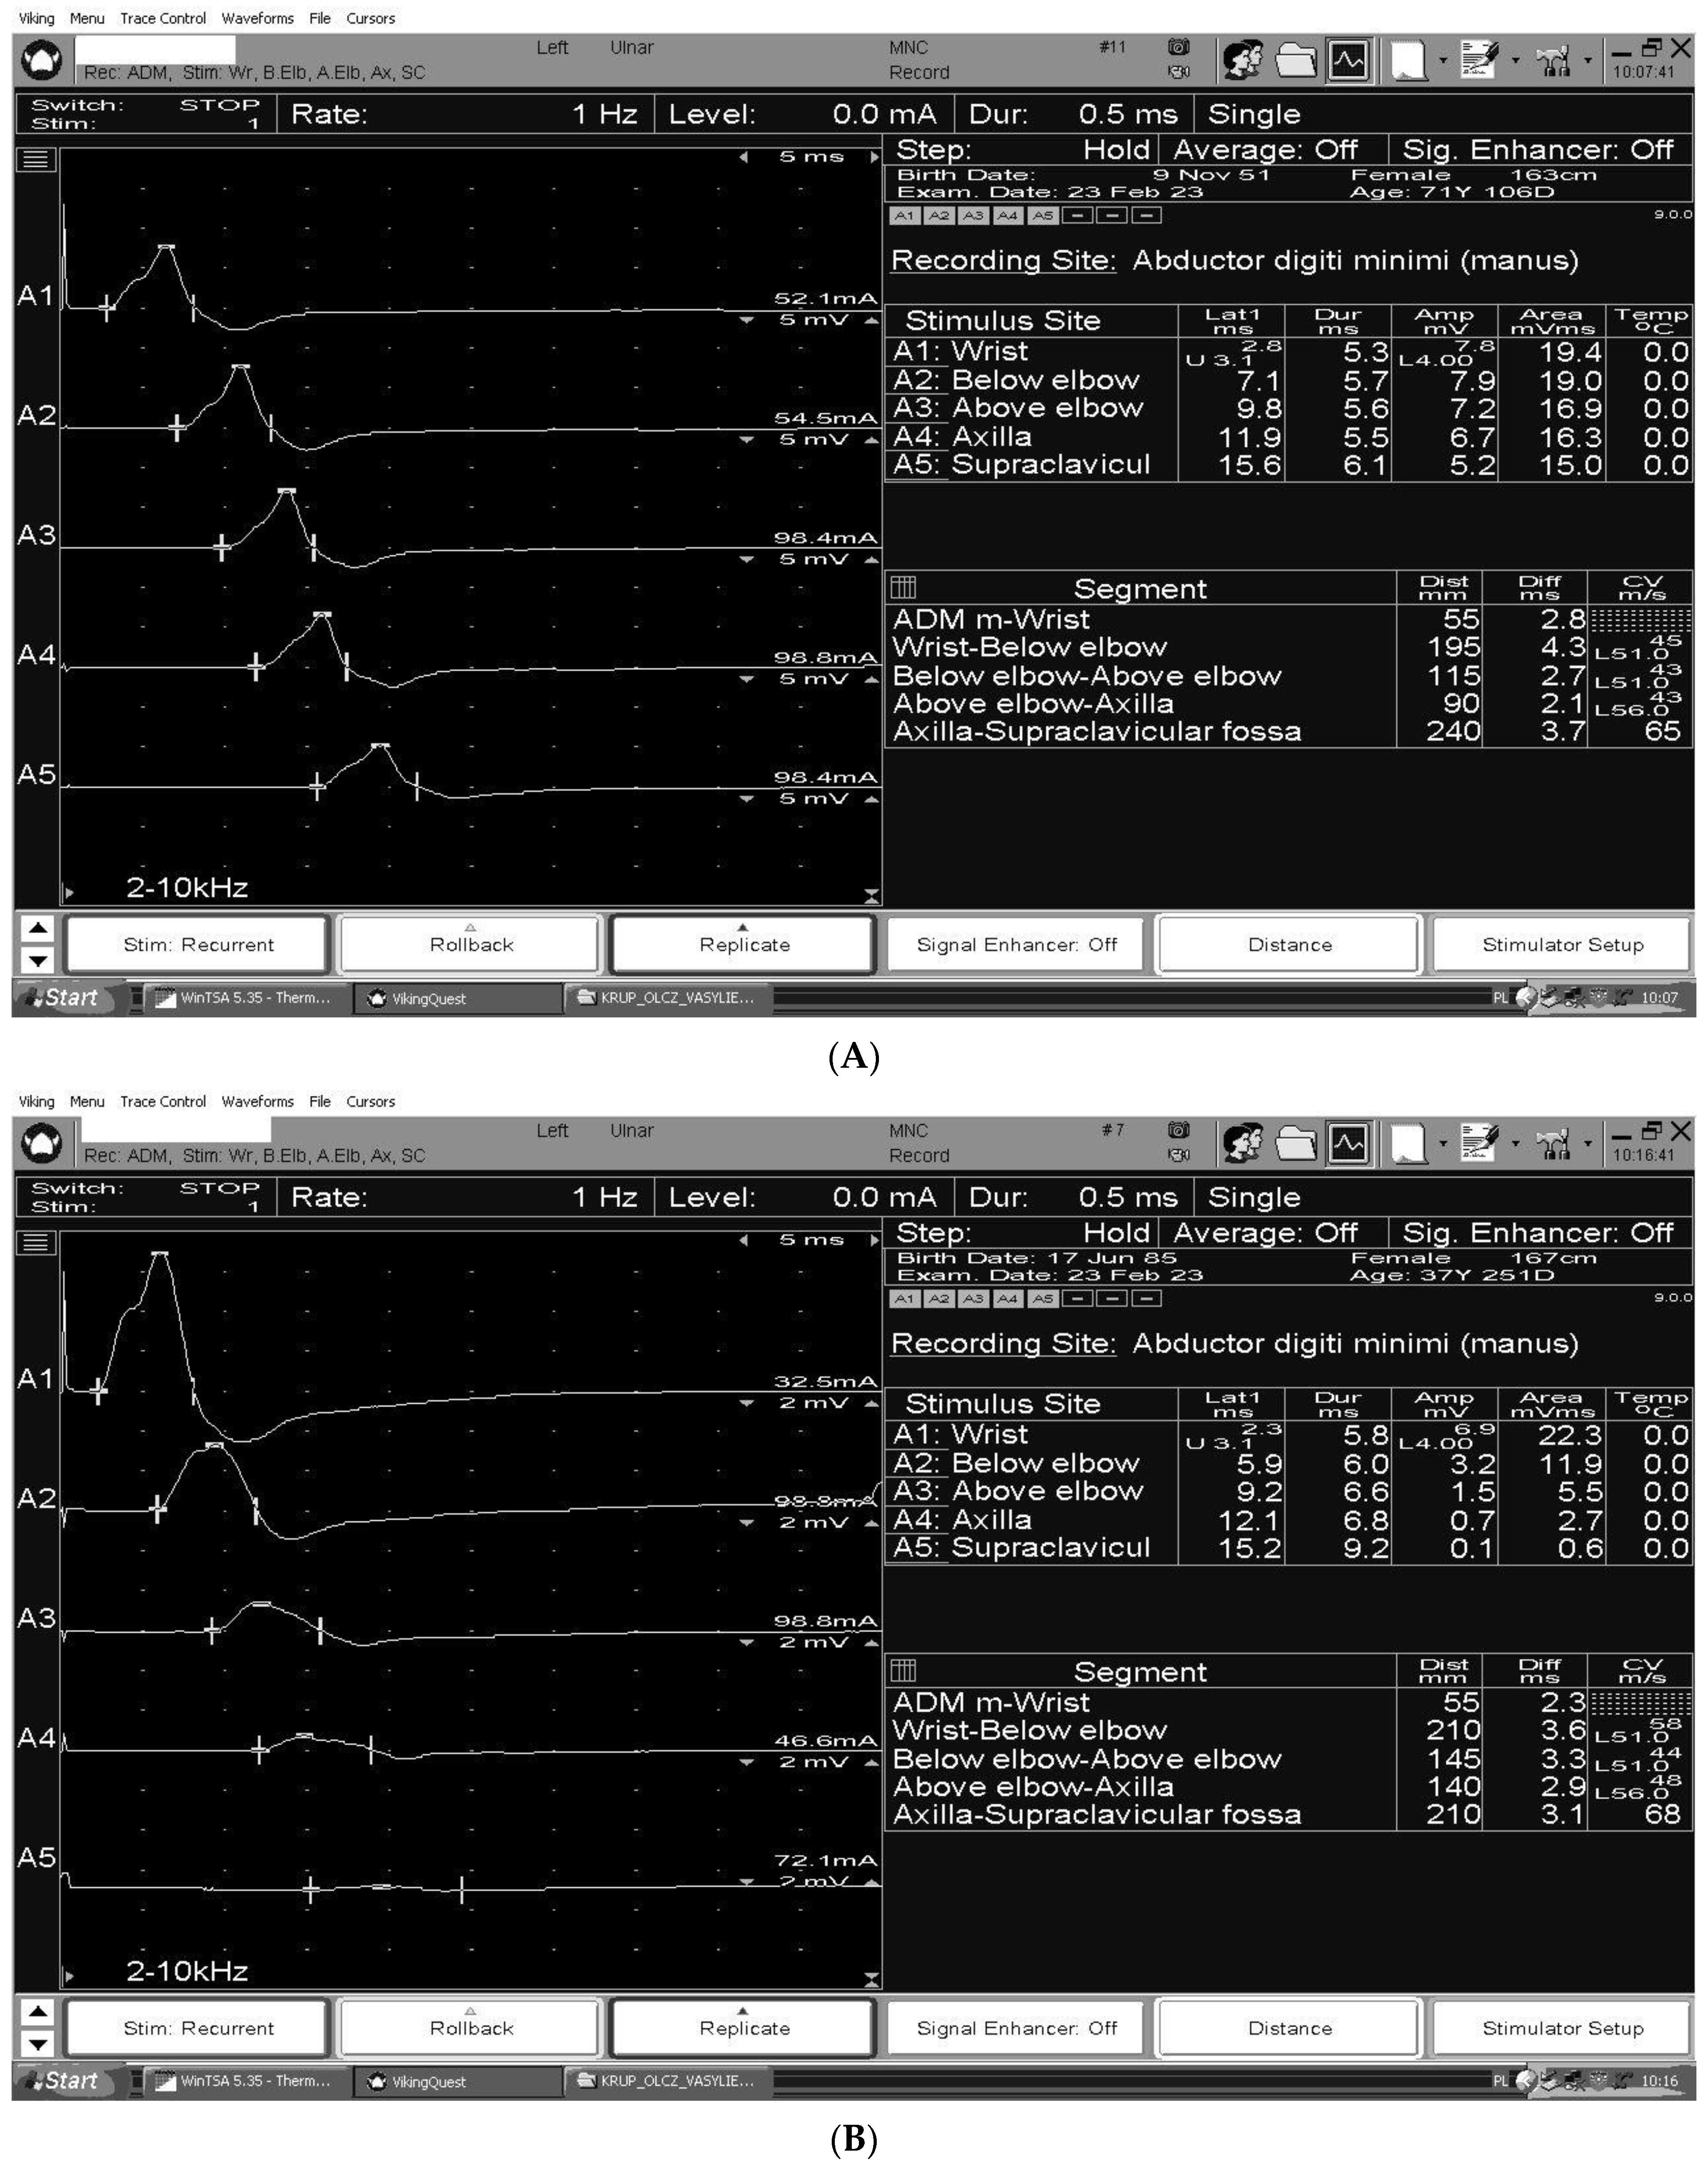

3. The Electrodiagnosis